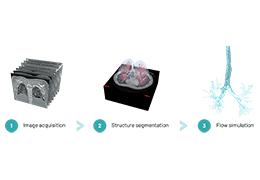

Performs 3D reconstruction and volume rendering.